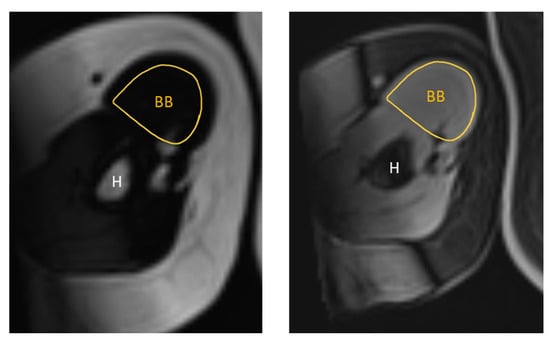

The MR images were qualitatively analysed using the institution’s picture archiving and communication system (PACS). The same anatomical landmarks were used as for the US images. For the RF muscle, this was midway between the anterior and superior iliac spine and the superior aspect of the patella. For the BB muscle, the ROI was two-thirds of the way between the acromion and the antecubital crease. The MRI measurements were obtained by manually tracing the cross-sectional boundary of the right RF and right BB, as shown in Figure 3 and Figure 4. The boundary segmentation measurement was copied from the water image to the fat image, so the CSA had the exact same size. Using the axial water and fat images of the RF and BB muscles, the MR %FF was calculated using the following formula: MR %FF = (signal-fat/[signal-water + signal-fat] × 100) [27]. Each operator then segmented magnetic resonance images, which a senior doctor with more than ten years of experience then reviewed.

Figure 4. Representative T1-weighted Dixon VIBE MR image tracing the cross-sectional area of the right BB on the fat-based image (left) and water-based image (right). BB = biceps brachii, H = humerus.